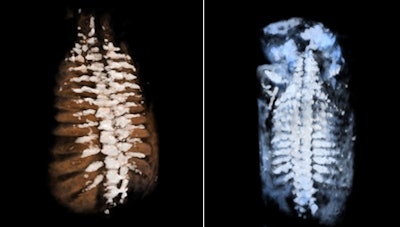

It is a great advantage to diagnose fetal skeletal dysplasia with 3D/4D technology because bone mineralization can be assessed and it is possible to compare bones (e.g., the spine with the skull bone and lavage bone), according to Dr. Peter Conner, PhD, of Karolinska University Hospital in Sweden. With 4D sequences, the fetal movement pattern and soft tissues can be assessed and, hence, malalignments can be diagnosed. Furthermore, with 4D it is possible to see fractures in both the lavage bone and ribs by using skeletal view visualization. In this mode, the skeletal structures are enhanced and soft tissues are suppressed.

A combination of better usage of 3D technology and knowledge of 3D technology in skeletal dysplasia will make it possible to correctly assess and diagnose many skeletal dysplasias in the first trimester. This is a major improvement, as most skeletal dysplasias are not currently diagnosed until the second or third trimester in families without a known family history of the condition, according to Conner. Adaptive volume enhancement technology, which suppresses unwanted signal such as noise/speckle, could also potentially facilitate the early diagnosis of skeletal dysplasias.

Fetal spine evaluated using skeletal view rendering with a sepia color map (left) and standard color map (right).In fetal brain examinations, 3D imaging provides a full volume of the fetal brain. Adaptive volume enhancement and true-to-data rendering -- which combines adaptive volume enhancement, scan conversion, and rendering to yield high resolution and fewer image approximations -- can also improve clinical value and make it easier to perform the study. 3D ultrasound fetal brain measurements are more accurate and reproducible than their 2D counterparts, according to Selbing.